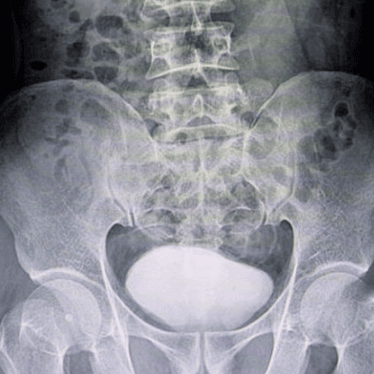

Julia learned she has scoliosis — a spine disease that affected the curvature of her back. This condition requires frequent imaging tests to guide care. Learn how Children’s The EOS system® helped providers diagnose and treat her disease with limited radiation exposure.